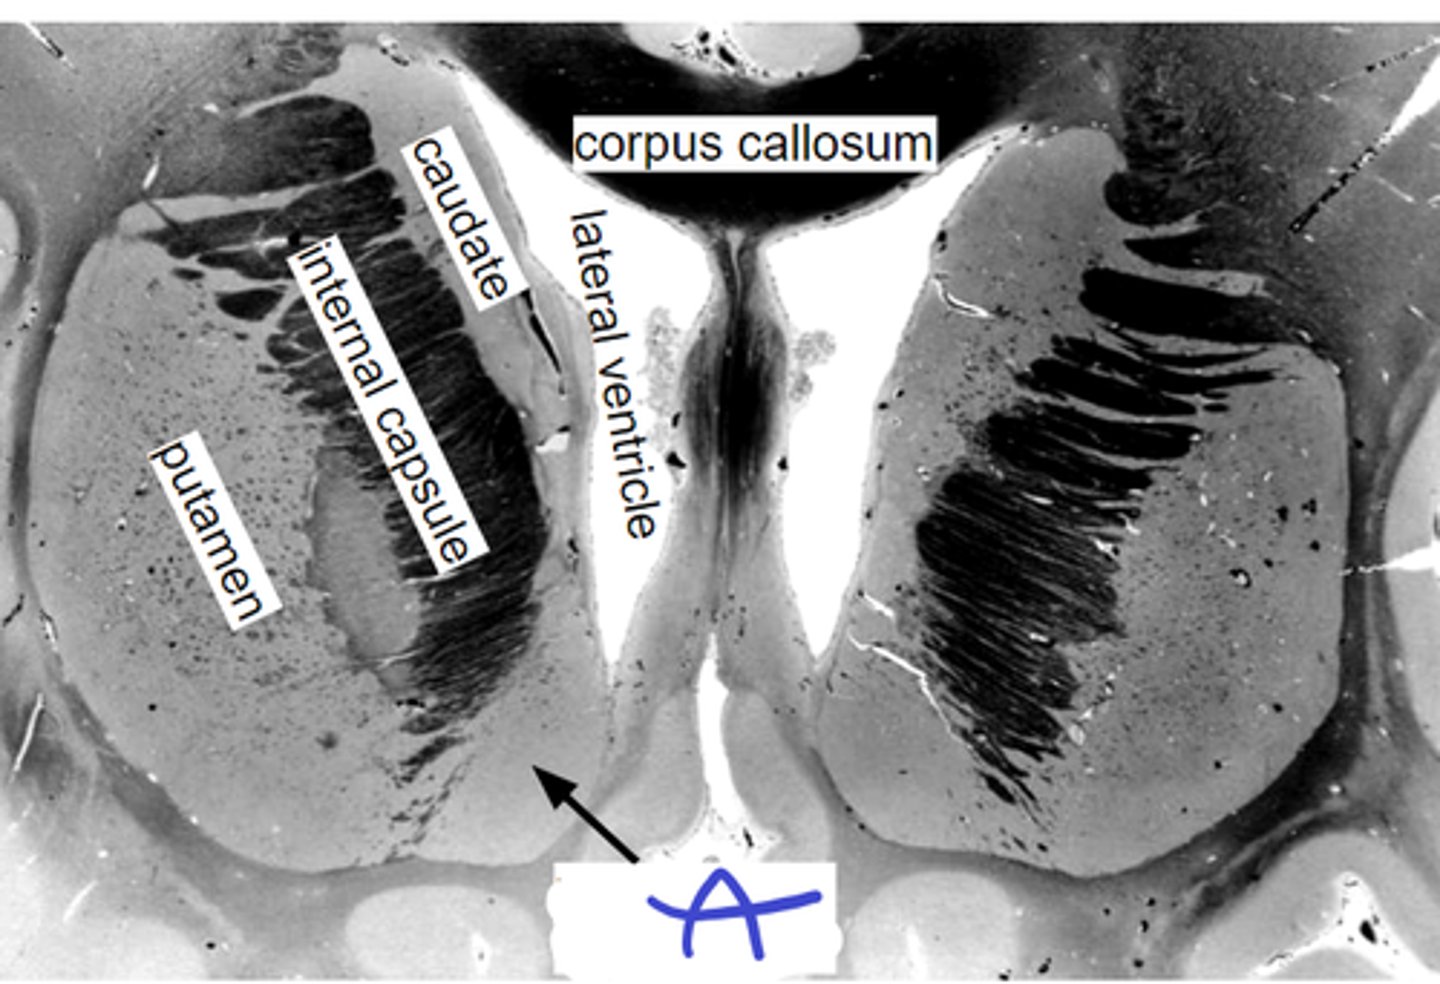

a-cingulate c

b-caudate n

c-internal capsule

d-putamen n

e-insula c

f-hypothalamus

abcdef